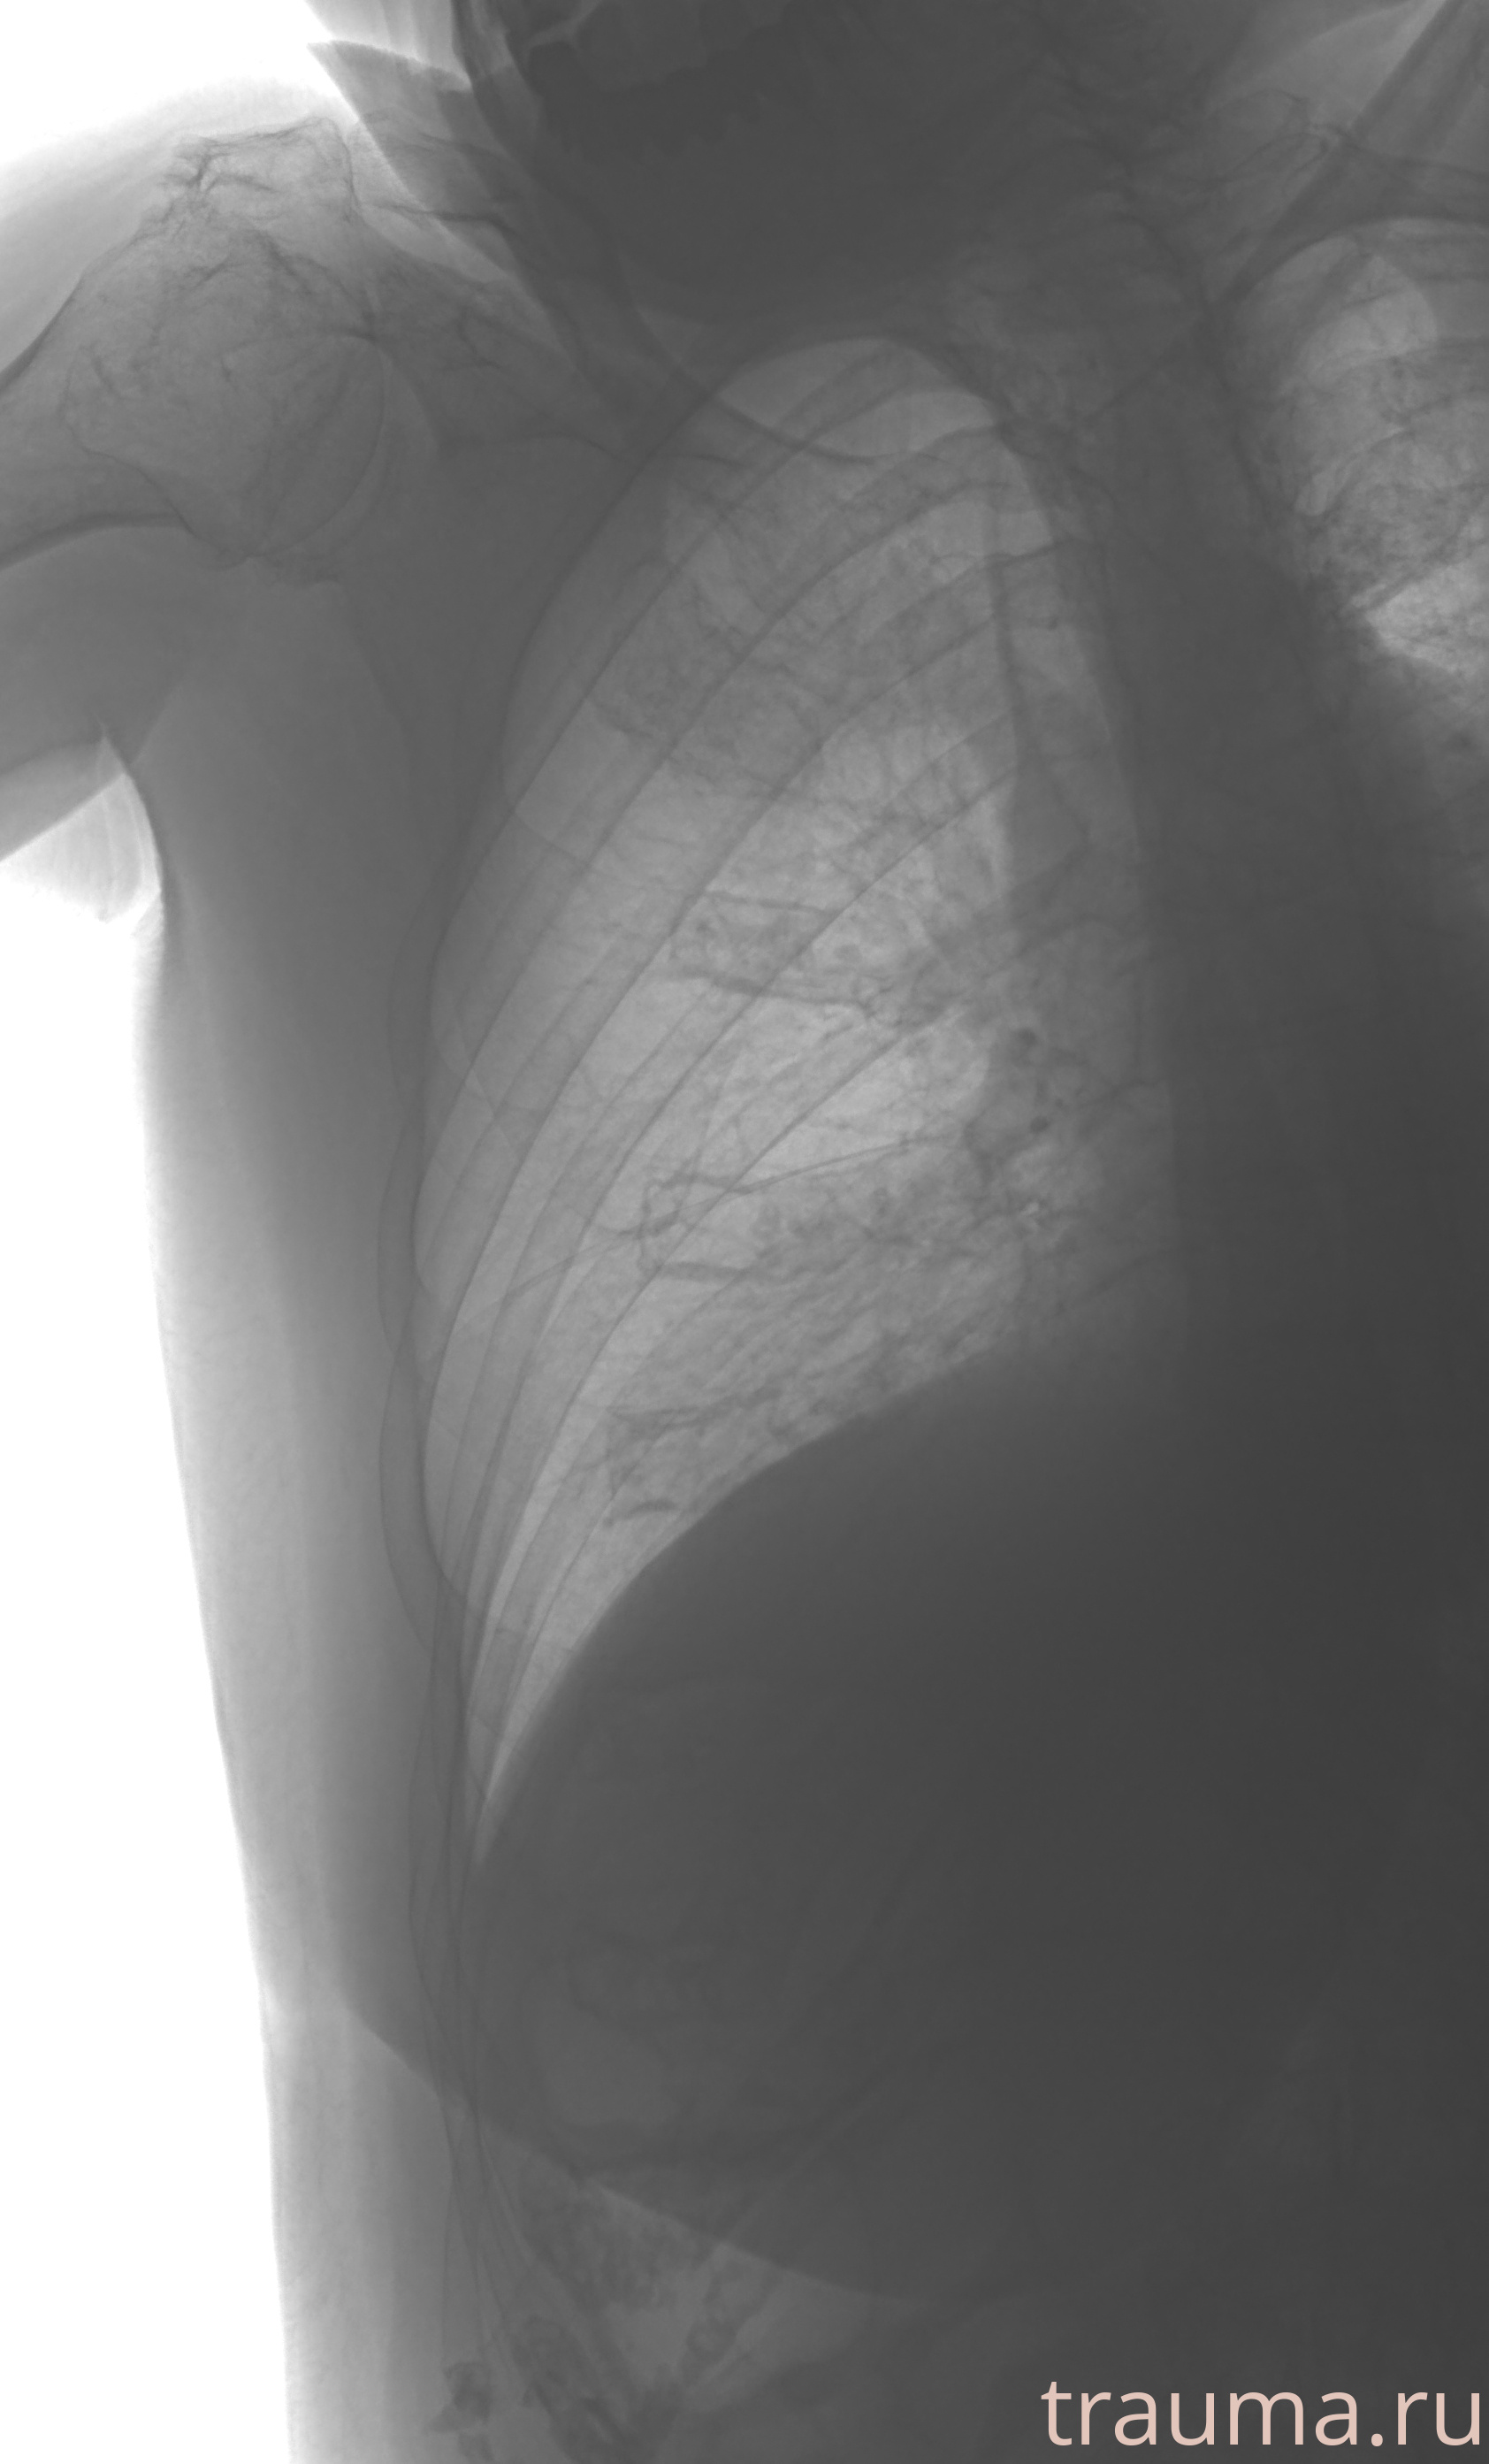

Рентгенограммы

Рентген на дому: по вашему адресу приезжает врач-рентгенолог, травматолог-ортопед с мобильным рентгеновским аппаратом, проводит диагностику травмы или заболевания, делает необходимые рентгенограммы, дает рекомендации по дальнейшему лечению. Получить качественные снимки в домашних условиях возможно благодаря уникальной методике, разработанной МосРентген Центром для института  Склифосовского